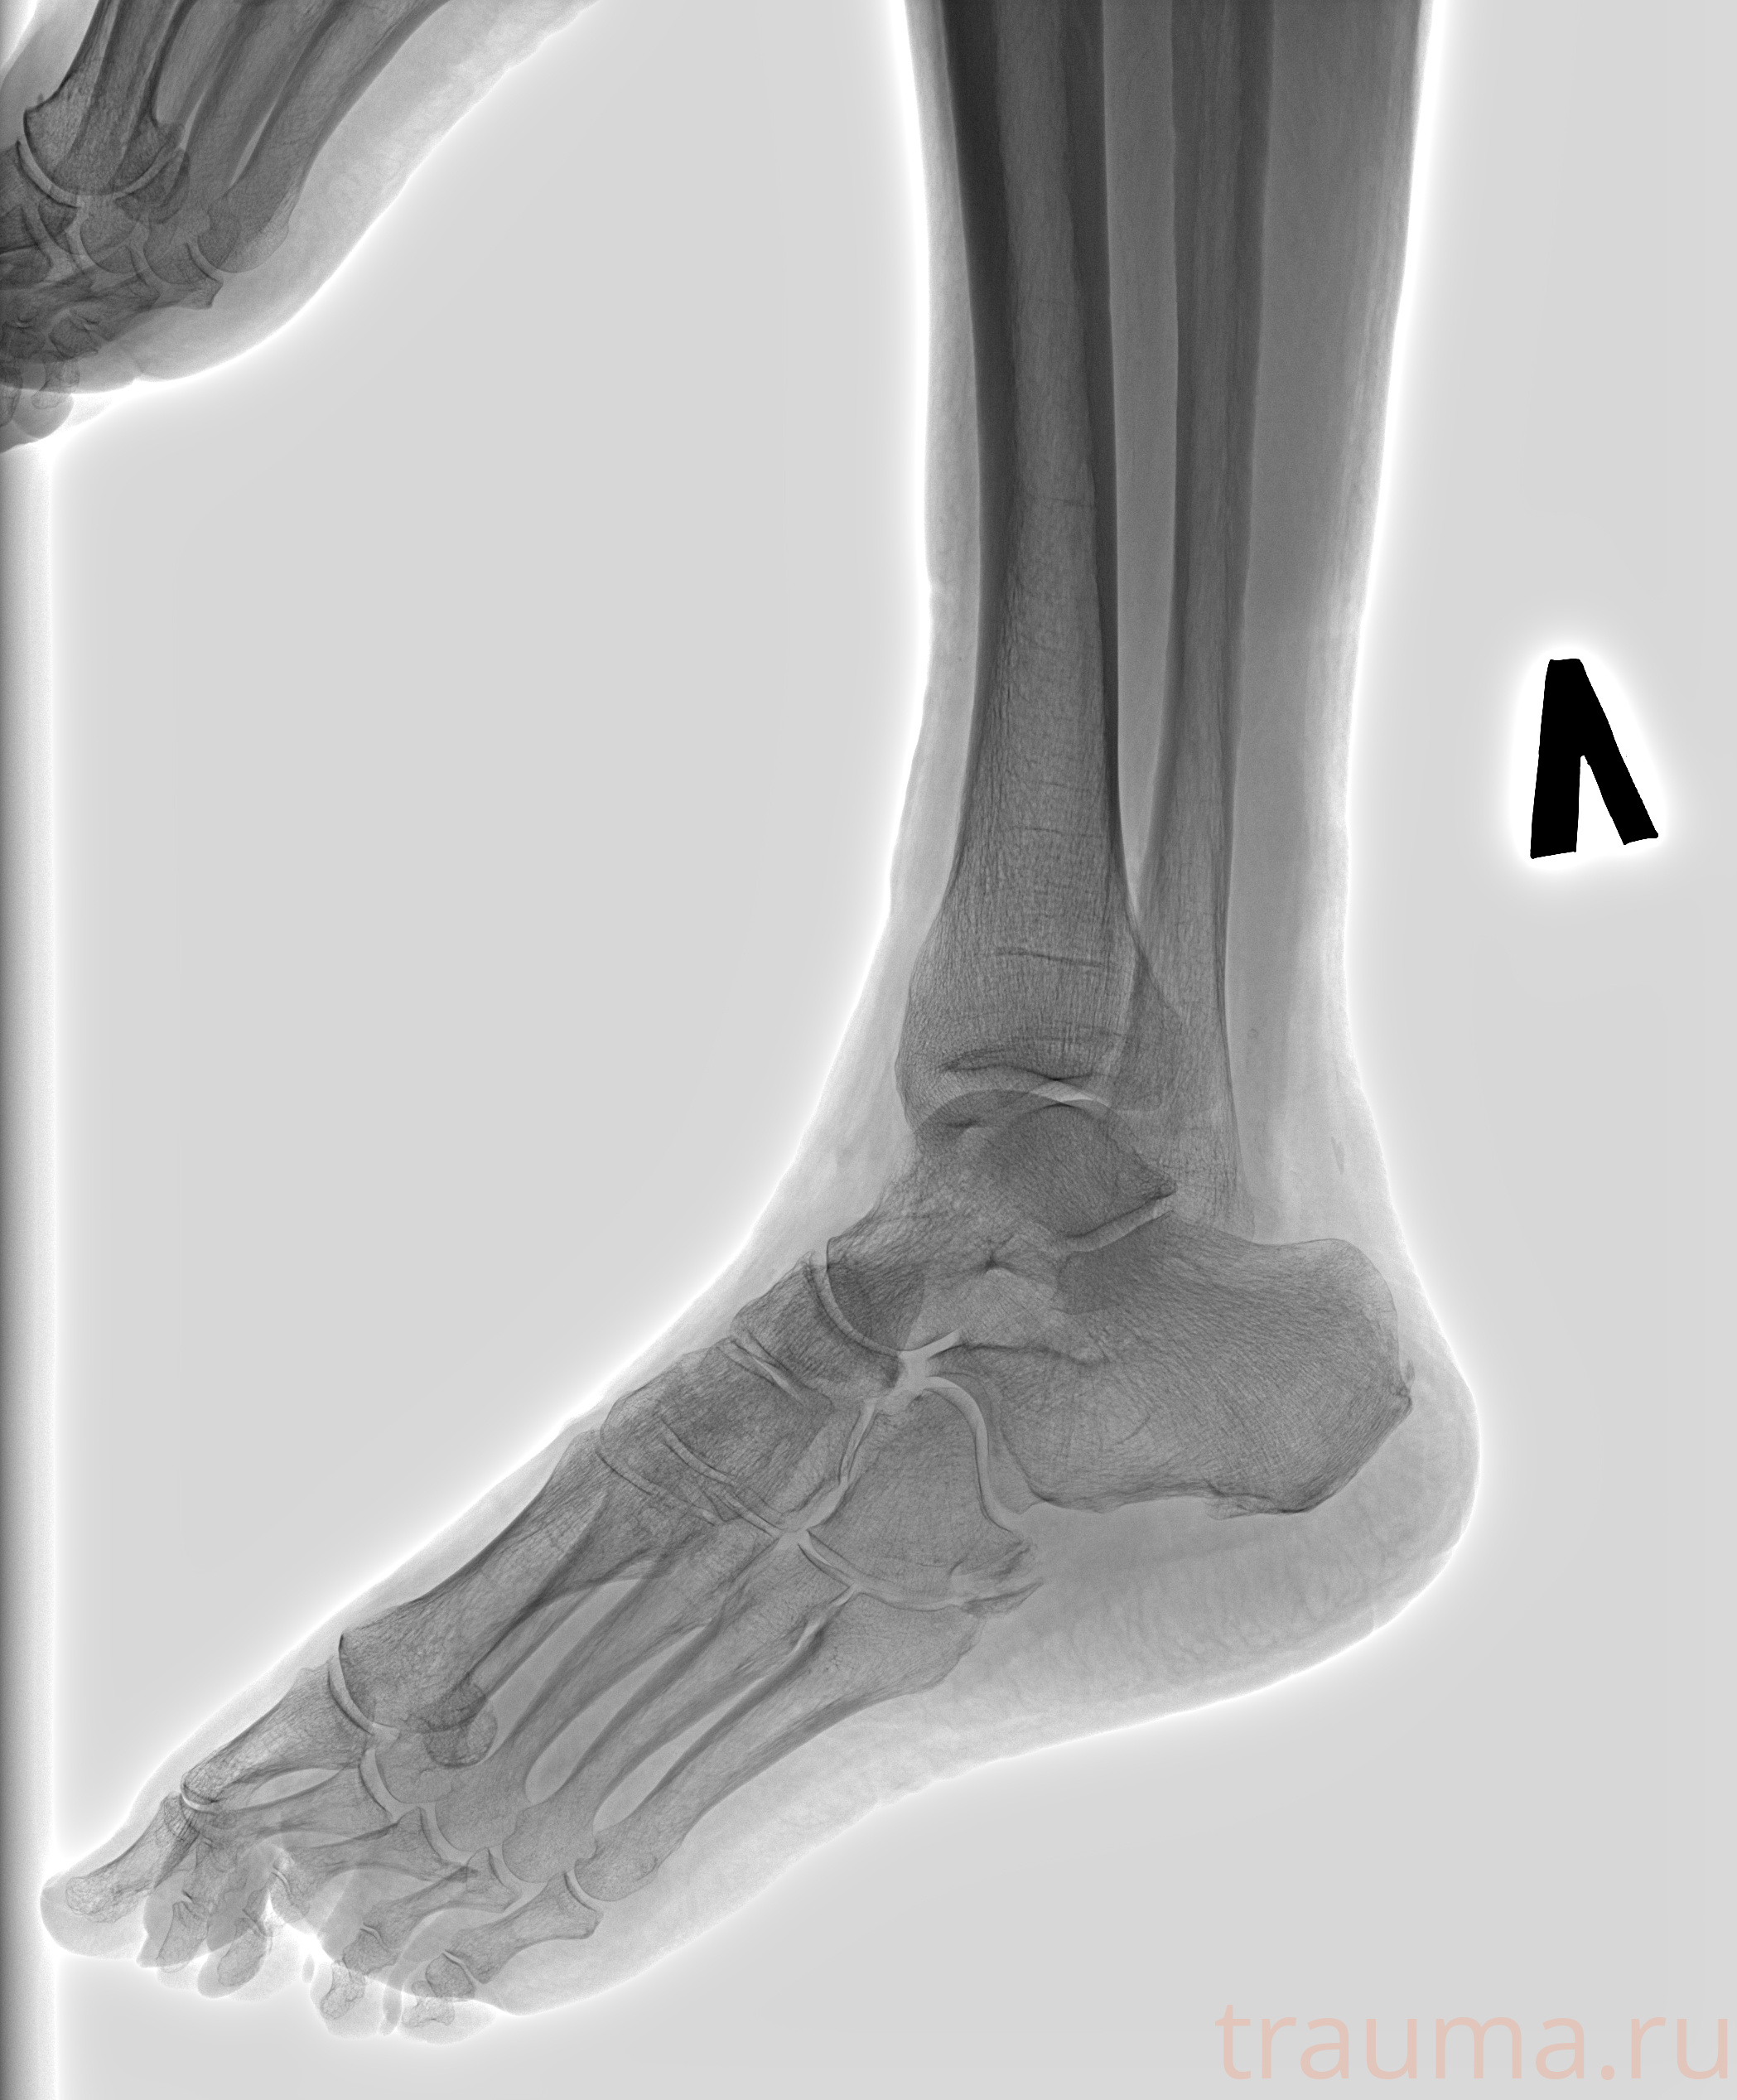

Рентгенограммы

Рентген на дому: по вашему адресу приезжает врач-рентгенолог, травматолог-ортопед с мобильным рентгеновским аппаратом, проводит диагностику травмы или заболевания, делает необходимые рентгенограммы, дает рекомендации по дальнейшему лечению. Получить качественные снимки в домашних условиях возможно благодаря уникальной методике, разработанной МосРентген Центром для института  Склифосовского